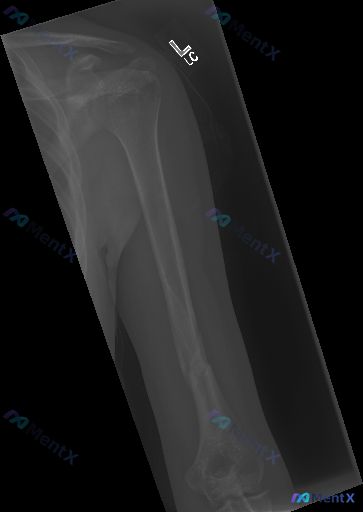

左侧肱骨正位X光片发现骨皮质连续性中断,这类表现最核心的判断与排查方向是什么?

整理到一份左侧肱骨正位X光片的影像资料,结合临床情况和大家讨论一下判断方向:

- 肱骨干中下段骨皮质连续性完全中断,可见斜形及部分螺旋形骨折线

- 骨折断端有明显向外侧成角移位,同时存在断端重叠(短缩移位)

- 骨折周围软组织可见轻度肿胀,密度均匀,无明显积气或异物

- 肩关节、肘关节结构基本对合,间隙未见明显异常;整体骨密度无弥漫性减低,无明显骨膜反应或骨质破坏/硬化灶

📋答案:结合完整资料分析,当前最优先的临床判断与处理方向是:首先重点排查桡神经功能(垂腕、虎口区感觉),再同步评估骨折与其他情况。